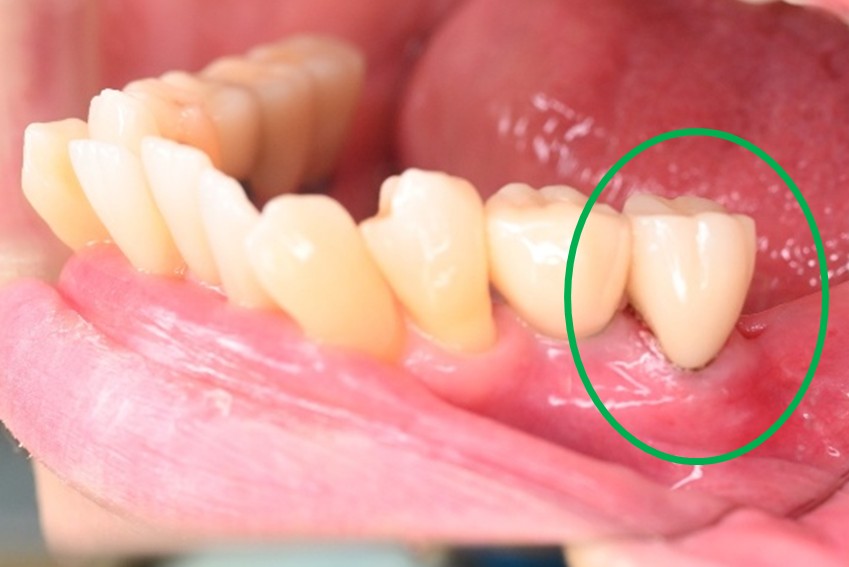

女性 Yさん 60代 (オールセラミック冠)

主訴

以前治療した右下の犬歯が、虫歯になり色が変わってきているので、治したい。

治療内容

根管治療をし、オールセラミック冠を被せました。

所感

神経が取り除かれ、歯自体が変色し、虫歯になっていました。根管治療をし、ファイバーコアを入れ、オールセラミック冠を被せました。

オールセラミック冠1本(失活歯):¥104,500(税込)

Before

After